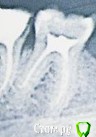

МарияМирабелла Опубликовано 27 марта, 2016 Поделиться Опубликовано 27 марта, 2016 http://s017.radikal.ru/i410/1603/ba/512b63cc361a.jpg Добрый вечер!Данный зуб (6-ка) лечила 16 лет назад. Сейчас решила одеть на него коронку. Так как из-за старого метода пломбировки канала - зуб покраснел и не нравится его внешний вид. К тому же пломба довольно обширная, в общем боюсь за этот зуб. Подскажите, хорошо ли пролечены и запломбированы канала (это 16 лет тому назад)? Или надо по новой пломбировать каналы? Читала, что резорцин-формалиновые каналы плохо поддаются перелечиванию - не расширяются и можно их повредить вплоть до перфорации?Подскажите нормально у меня пролечены каналы?Заранее спасибо! Ссылка на комментарий

IvanK Опубликовано 30 марта, 2016 Поделиться Опубликовано 30 марта, 2016 Здравствуйте. Снимок не очень хорошего качества. Нужно смотреть. Бывает, что в каналах "каша".. 1 Ссылка на комментарий

M@estro Опубликовано 31 марта, 2016 Поделиться Опубликовано 31 марта, 2016 Здравствуйте.Снимок не очень хорошего качества. Нужно смотреть. Бывает, что в каналах "каша".. А сколько споров было ) Согласен , нужно снимать старую пломбы ( перед протезированием это обязательно делается в любом случае) - и оценивать состояние зуба непосредственно внутри. При плотной пломбировке корневых каналов,отсутствии трещин зуба ; симптоматики и признаков воспаления на снимке - можно протезировать. Ссылка на комментарий